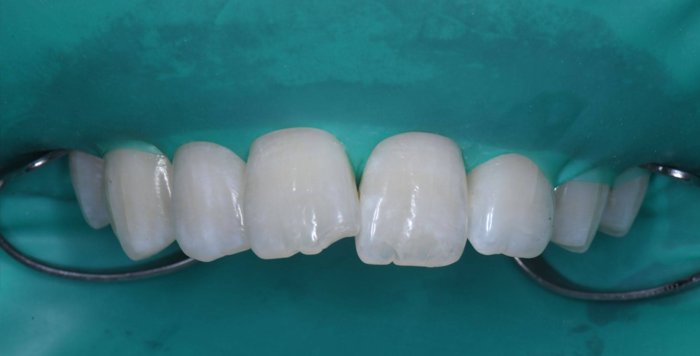

症例2:欠けた歯を治したい

治療前

治療後

治療中の様子

修復した最後に、酸素で阻害された表面(Oxygen Inhibitation Layer)を最終重合しています。

| 主訴 | 欠けた歯を治したい |

|---|---|

| 治療期間 | 1日 |

| 治療費 | ¥22,000 |

| 治療内容 | コンポジットレジンにて修復しました。切端の透明感や亀裂(クラック)を隣の歯と同じように再現できました。患者様には大変満足していただけました。 |

| 治療のリスク | 欠けたり、経年的な変色の可能性があります。 |